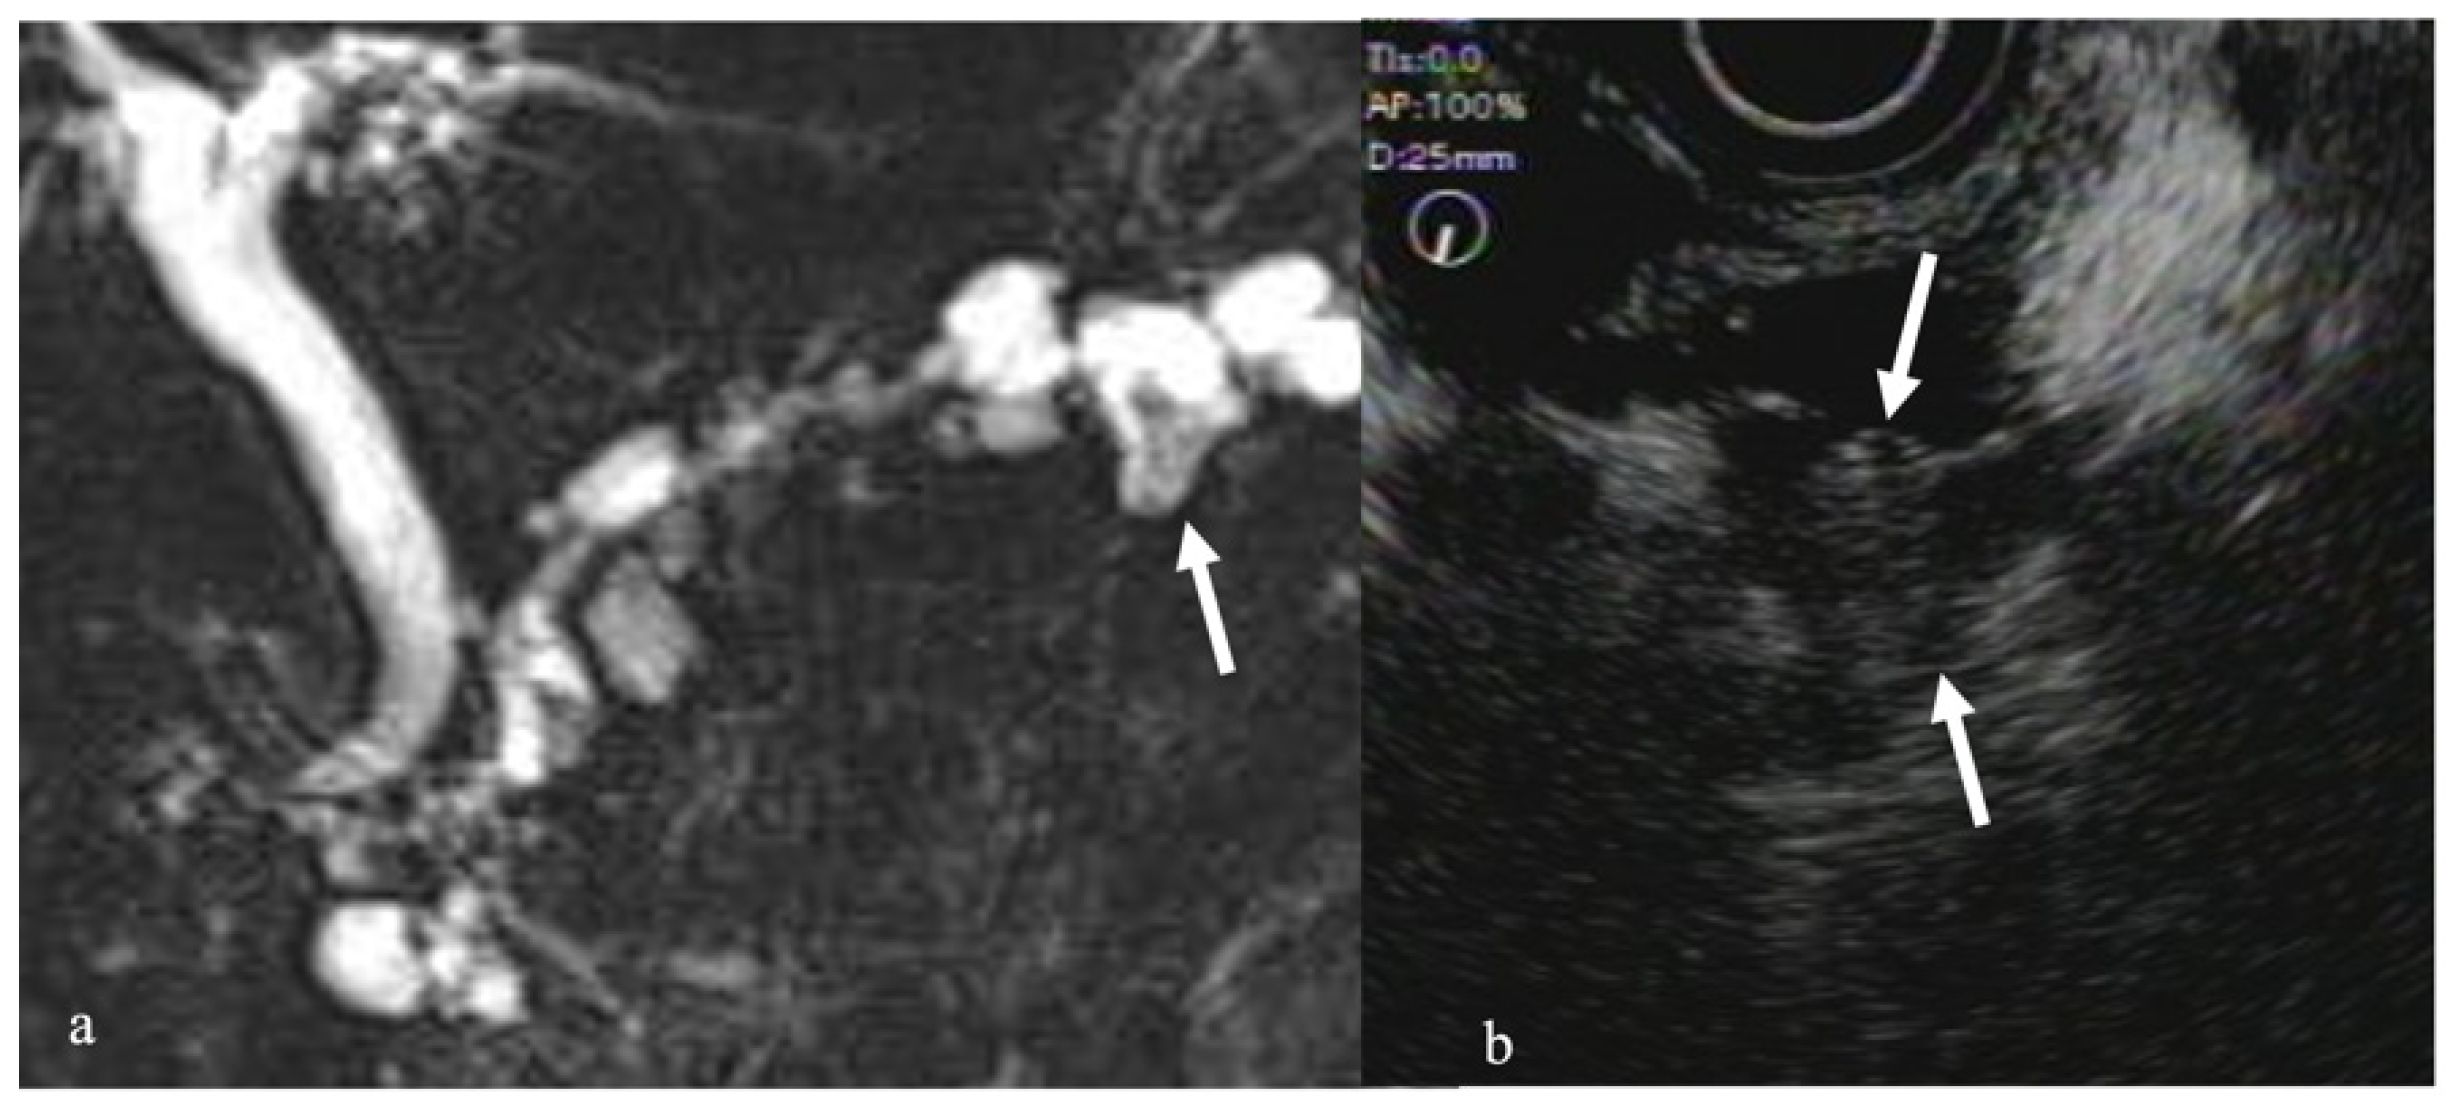

- Harima, H.; Kaino, S.; Shinoda, S.; Kawano, M.; Suenaga, S.; Sakaida, I. Differential diagnosis of benign and malignant branch duct intraductal papillary mucinous neoplasm using contrast-enhanced endoscopic ultrasonography. World J. Gastroenterol. 2015, 21, 6252–6260. [Google Scholar] [CrossRef]

- Yamashita, Y.; Ueda, K.; Itonaga, M.; Yoshida, T.; Maeda, H.; Maekita, T.; Iguchi, M.; Tamai, H.; Ichinose, M.; Kato, J. Usefulness of contrast-enhanced endoscopic sonography for discriminating mural nodules from mucous clots in intraductal papillary mucinous neoplasms: A single-center prospective study. J. Ultrasound Med. 2013, 32, 61–68. [Google Scholar] [CrossRef]